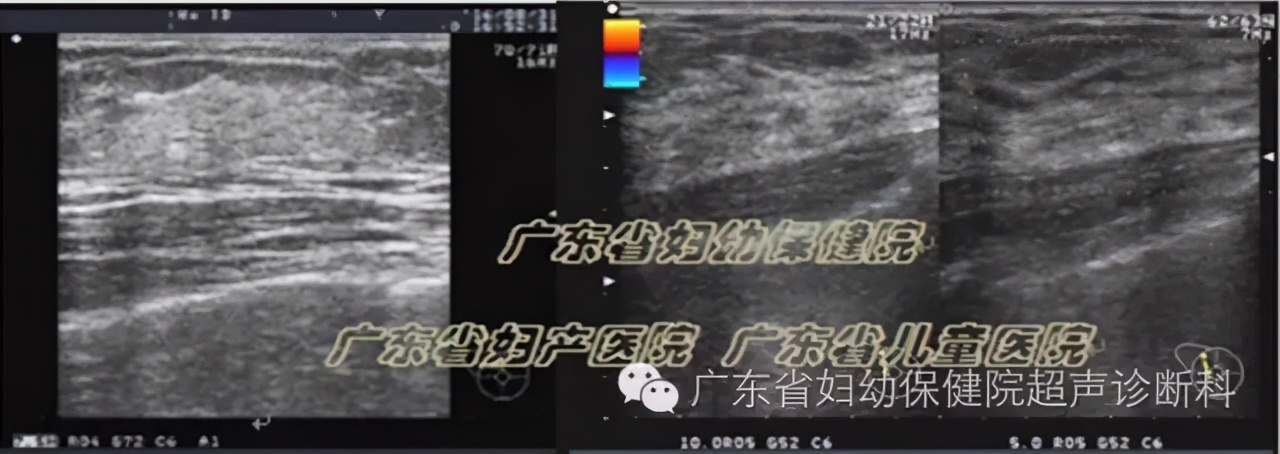

超声图像